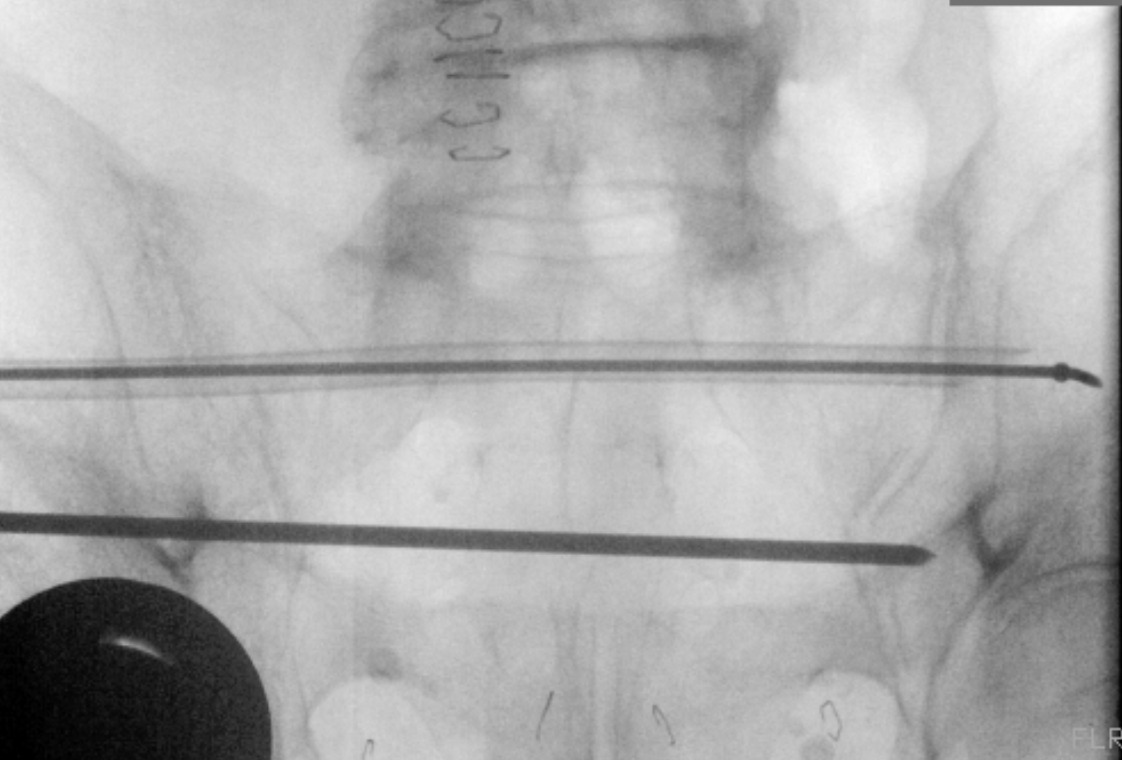

An exchange tube is placed over the steerable guidewire fully through the intraosseous channel (Figure 2). The guidewire is removed while making sure the exchange tube remains in place. A 1.6mm driving guidewire is inserted into the exchange tube. The exchange tube is then removed.

The CurvaFix implant is attached to the inserter and torque handle, then advanced over the driving guidewire using the torque handle. Once the implant is seated, the handle is turned until the inserter fins are parallel to the ground. The guidewire is removed, then the locking mechanism is activated. The inserter and torque handle are removed (Figure 3).